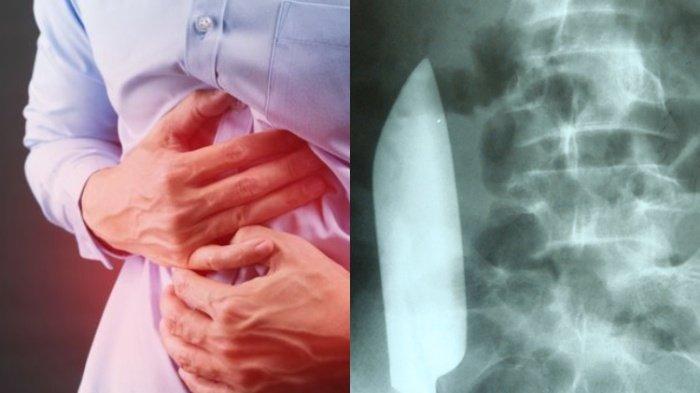

Fakta Ngeri Pria Sakit Perut Ternyata Ada Pisau Dalam Tubuh, Sebelumnya Berkelahi saat Mabuk

SURYA.CO.ID - Fakta ngeri datang dari seorang pria yang mengaku sakit perut, ternyata ada pisau di tubuhnya.

Keberadaan pisau di dalam perut pria yang mengaku sakit perut itu pun berhasil membuat geger.

Terlebih, pisau yang bersarang di dalam perut tersebut berukuran cukup besar.

Pisau itu memiliki panjang kurang lebih 15 cm.

Keberadaan pisau di dalam perut itu terungkap usai dokter melakukan rontgen.

Rupanya, pisau itu masuk ke dalam tubuh sang pria saat perkelahian tersebut berlangsung.

Beruntung, benda tajam tersebut berhasil dikeluarkan sebelum melukai organ-organ di dalamnya.

Pasalnya berdasarkan pernyataan dokter, keberadaan pisau di dalam perut bisa sangat membahayakan.

Bahkan, bisa mengancam nyawa pria tersebut.

Diketahui, pria yang belum diketahui namanya tersebut berasal dari Nepal.

Ia merupakan pemuda 22 tahun.